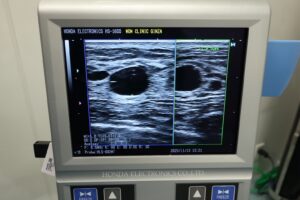

実際のしこりのエコー画像

※他院で施術を受けてしこりができた患者様のエコーのお写真

こちらは過去に他院で脂肪注入で豊胸を受けた患者様の、しこりが写っている実際のエコー写真です。しこりによって見た目の違和感があるだけではなく、周囲の血行が妨げられている状態が確認できます。

放置すると中心部の壊死した部分が液状化するオイルシスト、または被膜部分が硬くなる石灰化として塊として残るケースがあります。細胞が密に残る充実性のしこりに移行したり、炎症が続いて瘢痕化(線維化)し、硬さや変形が目立つようになる可能性も否めません。

このようなしこりは、自然に吸収されることが少なく、時間の経過とともに硬さや大きさが増していく傾向にあります。さらに、石灰化が進むとエコーやマンモグラフィで乳腺の病変と判別しにくくなることもあり、診断上の支障をきたす場合もあります。